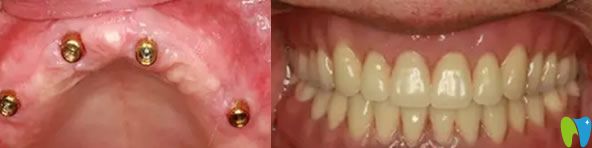

雅悅齒科全口無牙種植牙前后效果對比圖

老媽的牙齒,可能因?yàn)樯盍?xí)慣的原因,導(dǎo)致牙齒脫落嚴(yán)重,按了活動假牙,當(dāng)時對于口腔牙齒也不是很了解,覺著活動假牙價格合適。按上之后,感覺強(qiáng)度不是太好,吃東西容易塞牙,造成目前,牙齦有點(diǎn)萎縮。來院經(jīng)過王杰院長檢查后,需要對牙齦萎縮進(jìn)行治療,炎癥得到控制后在再進(jìn)行種植牙修復(fù)。

經(jīng)過一個月的漫長等待,老媽終于做了種植牙,當(dāng)場就拿蘋果做實(shí)驗(yàn),感覺種出來的牙齒和真牙一樣舒服。老媽再次擁有滿口舒適的好牙,恢復(fù)了咀嚼功能,真心覺得很不錯,感覺醫(yī)生技術(shù)水平也很專業(yè),很細(xì)心,走的時候還給我們囑咐種植牙的術(shù)后護(hù)理方法。

老媽種植牙的術(shù)后效果真實(shí)照片